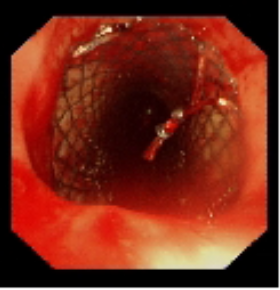

术前气管重度狭窄

术中植入金属覆膜支架

针对患者气道狭窄危象,呼吸与危重症医学科联合麻醉科、医学影像科等多学科团队制定个性化方案。术中采用全身麻醉联合喉罩通气,通过硬质支气管镜与软镜协同操作,在狭窄段实施肿瘤冷冻切除,随后精准植入Y型金属覆膜支架。手术全程动态监测生命体征,最终支架释放位置理想,管腔扩张充分。术后复查显示气道通畅性恢复,患者血氧饱和度稳定在93%-97%。